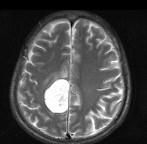

问题 男,68岁,头痛头昏、左侧肢体肌力减退3个月余,请根据所提供图像,选择最可能的诊断()

选项 A.(右顶叶镰旁)恶性脑膜瘤 B.(右顶叶镰旁)胶质瘤 C.(右顶叶镰旁)血管外皮瘤 D.(右顶叶镰旁)脑膜瘤(血管瘤型) E.(右顶叶镰旁)转移瘤

答案 D